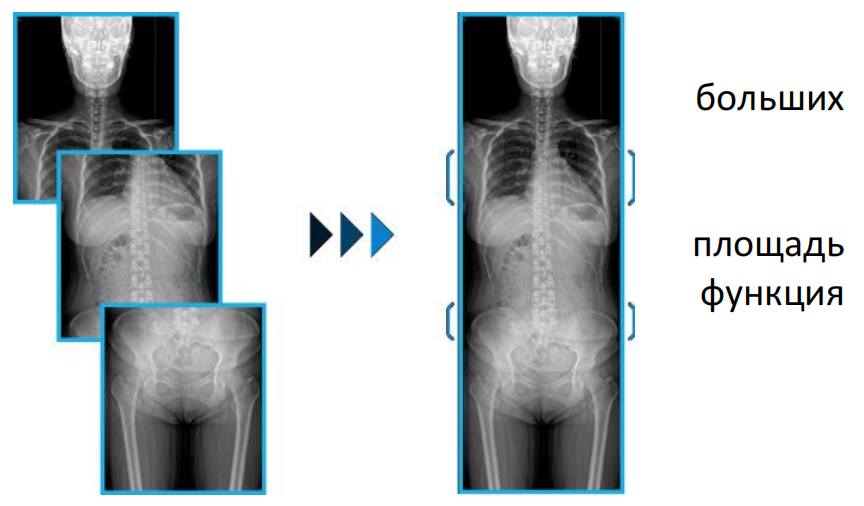

Сшивка (до 3-х снимков)

Простота визуализации анатомических структур больших размеров, без потери информации при сшивке. Алгоритм ручной сшивки позволяет

выполнить визуализацию частей тела, чей размер превышает площадь детектора. После получения нескольких снимков, эта функция значительно упростит процесс их совмещения в единое изображение.